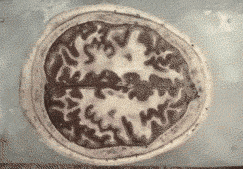

这是他今天演讲的PPT